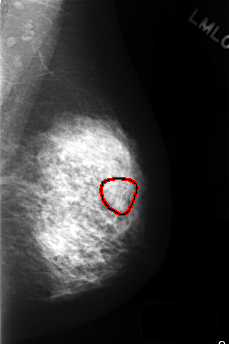

C_0412_1.LEFT_MLO

LEFT_MLO LINES 4472 PIXELS_PER_LINE 2976 BITS_PER_PIXEL 12 RESOLUTION 50 OVERLAY

FILE: C_0412_1.LEFT_MLO.OVERLAY

TOTAL_ABNORMALITIES 1

ABNORMALITY 1

LESION_TYPE MASS SHAPE ROUND MARGINS OBSCURED

ASSESSMENT 3

SUBTLETY 3

PATHOLOGY BENIGN

TOTAL_OUTLINES 1

BOUNDARY